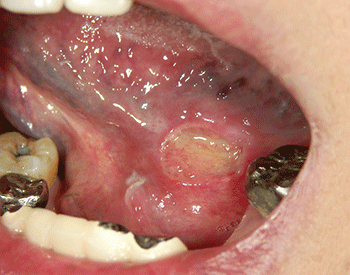

図❶ 左口底部に境界の明瞭な潰瘍を認める

現症:左口底部に12x10mm大の疼痛を伴う浅い潰瘍を認めた(図1)。潰瘍面は平坦であり偽膜の形成などはみられず、潰瘍周囲にわずかな隆起がみられたが、硬結は触知しなかった。